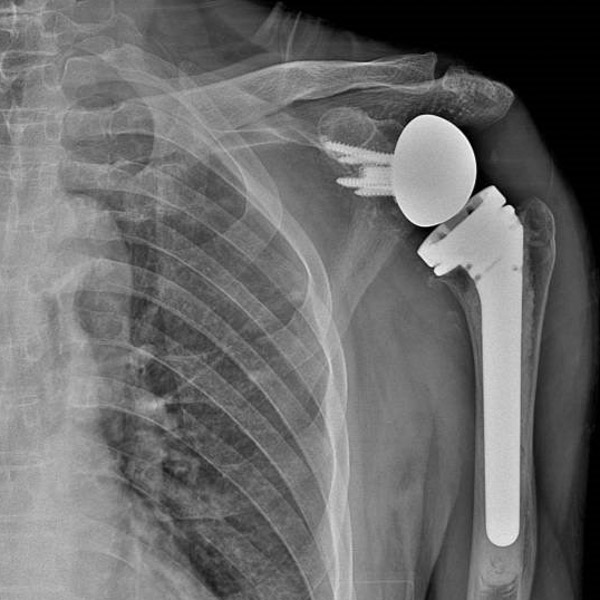

▲術前術后對比

“這種情況保守治療的效果不會太好,為最大程度恢復肩關節功能,就需要為患者進行左側反向全肩關節置換手術。”創傷骨科副主任舒文介紹,反向全肩關節置換手術是將組成整個肩關節的肱骨頭、肩胛骨關節盂全部換成人工的,并將肱骨頭與肩胛骨關節盂位置對調——假體的“肱骨頭在上、肩胛骨關節盂在下”,和人體真正的肩關節方向相反。這是近年國際上用來治療巨大不可修復肩袖損傷等復雜肩關節疾病的最新、有效技術。

幾天后,江爺爺被推進了手術室,由于進行了多次預演,手術過程非常順利,術中處理關節面、置入假體,關節穩定不易脫位,透視見假體位置良好,修補重建肩袖和關節囊……一個多小時以后,手術圓滿結束。